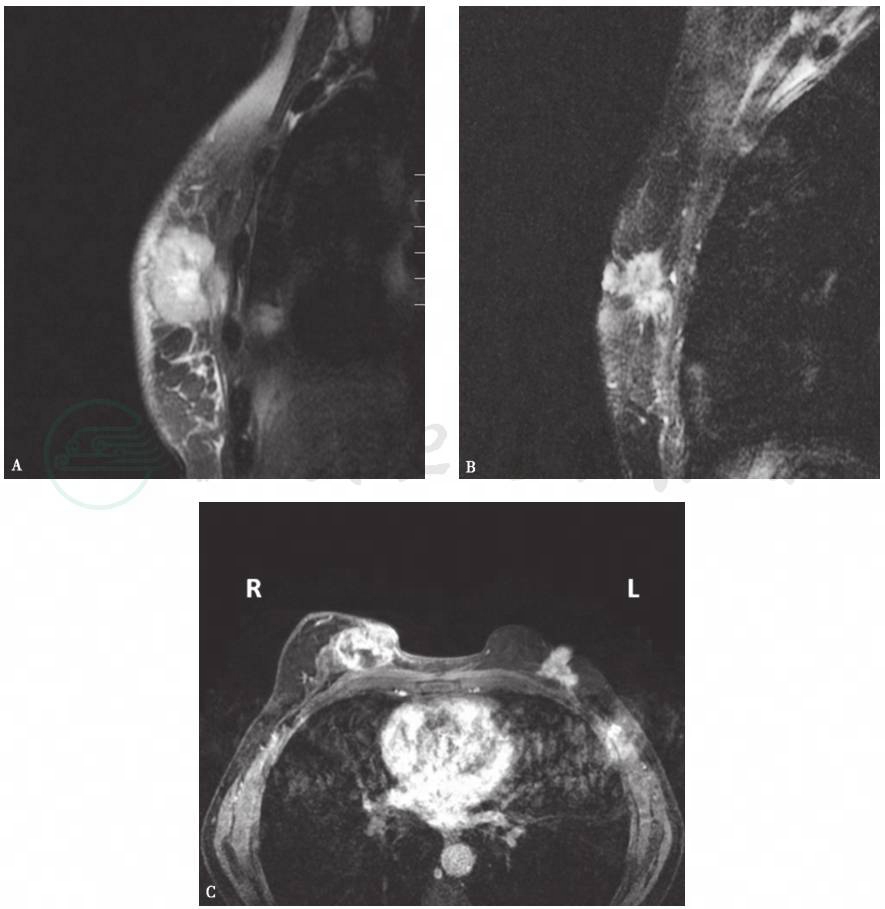

图2 双侧乳腺癌MRI

双侧乳腺内见不规则长T2信号肿物,右侧较大,增强扫描不均匀环形强化,右乳皮肤增厚,左乳头受累凹陷